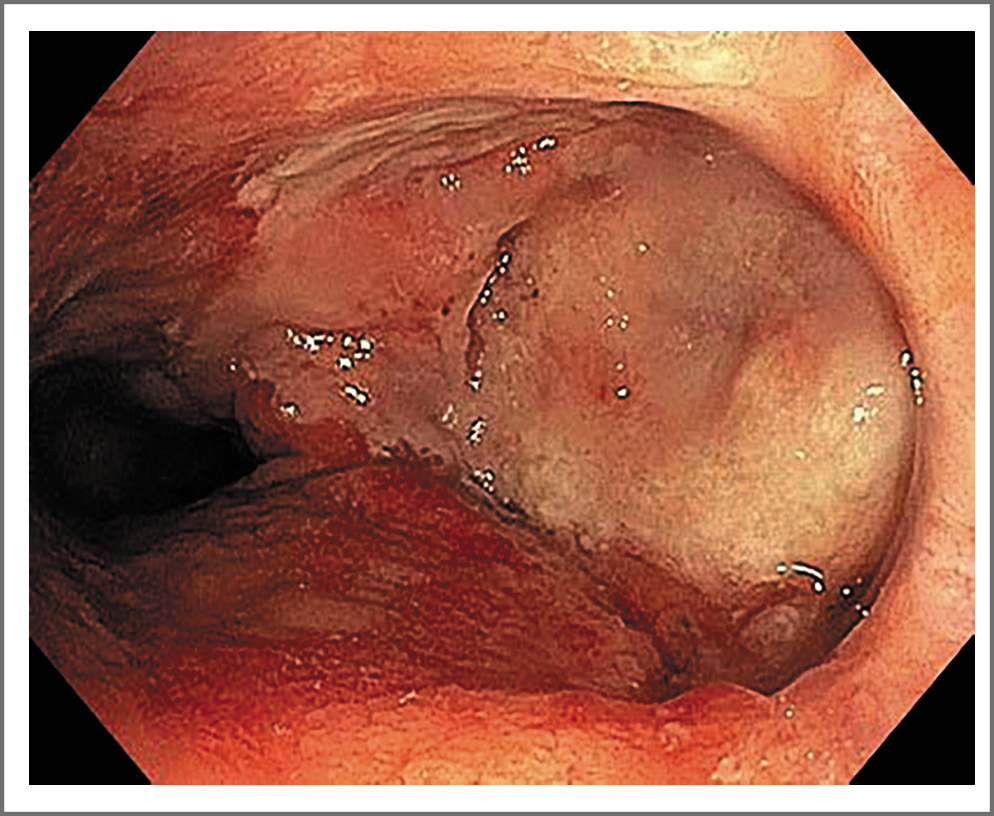

С учетом длительно сохраняющихся повреждений слизистой оболочки прямой кишки рекомендовали наложение петлевой сигмостомы. Послеоперационный период протекал без осложнений, пациента выписали в удовлетворительном состоянии. Рекомендовали консервативное лечение препаратами 5-АСК, решение вопроса о реконструктивной операции через 6 мес. Пациент использовал ежедневное ректальное введение суспензии (в виде клизм) месалазина (Салофальк) 2 г/сут, чередуя с пеной месалазина (Салофальк) в той же дозе. Отмечался положительный клинический эффект (купирование болевого синдрома, исчезновение гематохезий). Пациенту рекомендовали курсы пребиотической терапии и колонопротекции 3 раза в год препаратом масляной кислоты (Закофальк). На фоне проводимой терапии пациенту 2 раза в год выполняли колоноскопию, где фиксировали положительную динамику – исчезновение некротизированных масс в области дефекта передней стенки, наличие фибрина в этой же области (рис. 1). Нормализовались показатели клинического анализа крови, С-реактивного белка. ПСА сохранился на нижнем пороговом уровне – 0,01 нг/мл.

Рис. 1. Колоноскопия от 21 декабря 2021 г. Налет фибрина и разрастание соединительной ткани в области дефекта передней стенки прямой кишки.

Fig. 1. Colonoscopy, December 21, 2021. Fibrin deposits and proliferation of connective tissue in the area of the defect in the anterior wall of the rectum.